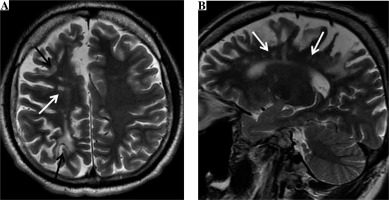

Two years after the cerebral vascular event resulting from wasp stings, the neurological examination of our patient revealed slight left hemiparesis with discrete spasticity of the lower limbs and with an extensor plantar response. The follow-up MR examination (Fig. 2) showed chronic external watershed ischemic lesions in the right hemisphere between the anterior and middle cerebral arteries and between the middle and posterior cerebral arteries. Moreover, there were chronic internal watershed lesions between the lenticulostriate and middle cerebral artery. Additionally, MR examination revealed moderate cortical and subcortical atrophy in this area.

Fig. 2

The brain magnetic resonance (MR) examination, axial (A) and sagittal (B) T2-weighted images reveal chronic external watershed ischemic lesions (black arrows) in the right hemisphere between the anterior and middle cerebral arteries and between the middle and posterior cerebral arteries (A). Moreover, there are chronic internal watershed lesions (white arrows) between the lenticulostriate and middle cerebral arteries